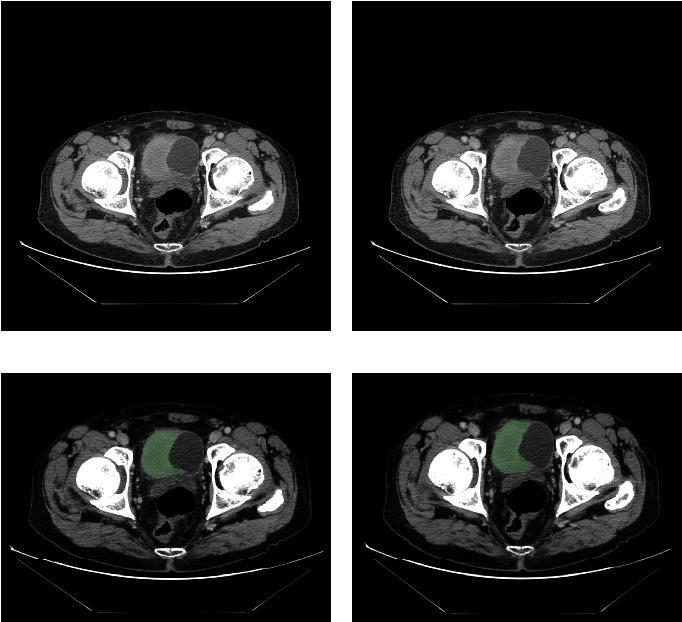

Bladder cancer has recently seen an alarming increase in global diagnoses, ascending as a predominant cause of cancer-related mortalities. Given this pressing scenario, there is a burgeoning need to identify effective biomarkers for both the diagnosis and therapeutic guidance of bladder cancer. This study focuses on evaluating the potential of high-definition computed tomography (CT) imagery coupled with RNA-sequencing analysis to accurately predict bladder tumor stages, utilizing deep residual networks. Data for this study, including CT images and RNA-Seq datasets for 82 high-grade bladder cancer patients, were sourced from the TCIA and TCGA databases. We employed Cox and lasso regression analyses to determine radiomics and gene signatures, leading to the identification of a three-factor radiomics signature and a four-gene signature in our bladder cancer cohort. ROC curve analyses underscored the strong predictive capacities of both these signatures. Furthermore, we formulated a nomogram integrating clinical features, radiomics, and gene signatures. This nomogram's AUC scores stood at 0.870, 0.873, and 0.971 for 1-year, 3-year, and 5-year predictions, respectively. Our model, leveraging radiomics and gene signatures, presents significant promise for enhancing diagnostic precision in bladder cancer prognosis, advocating for its clinical adoption.

Abstract Image